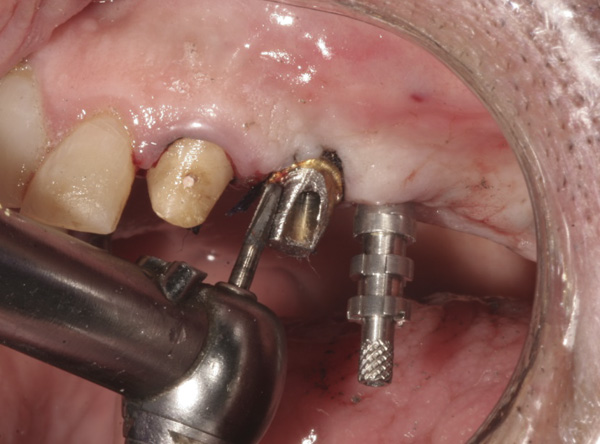

Results: A decision was made to re-prepare all of the abutments intraorally (Figure 3) so that all abutment margins would be at or below the gingival margin. (Of note, teeth Nos. 8 and 9, also shown in Figure 3, were later submerged for the case to be fully implant-supported.) While re-preparation greatly improved the esthetics of the final result, it required retraction cord placement, new impressions, and new castings.

(Note: A separate but similar type of case shown in Figure 4 and Figure 5 further illustrates intraoral abutment re-preparation.)

Figure 3 Abutments re-prepared intraorally.

Figure 3

Figure 4 Following osseointegration of an implant at No. 12, recession was observed at the fixture-level impression stage of No. 13; it was decided to re-prepare the margins of the CAD/CAM custom abutment of implant No. 12. Retraction cord was placed prior to preparation to avoid tissue injury and improve visibility of both tooth No. 11 and the implant custom abutment margin. As expected, recession was greater along the distal side of abutment No. 12, adjacent to the healed extraction/newer implant site.

Figure 4

Figure 5 Newly placed custom abutment on No. 13 with the previously re-prepared abutment at No. 12. No new recession has occurred since the case was completed more than 3 years ago.

Figure 5